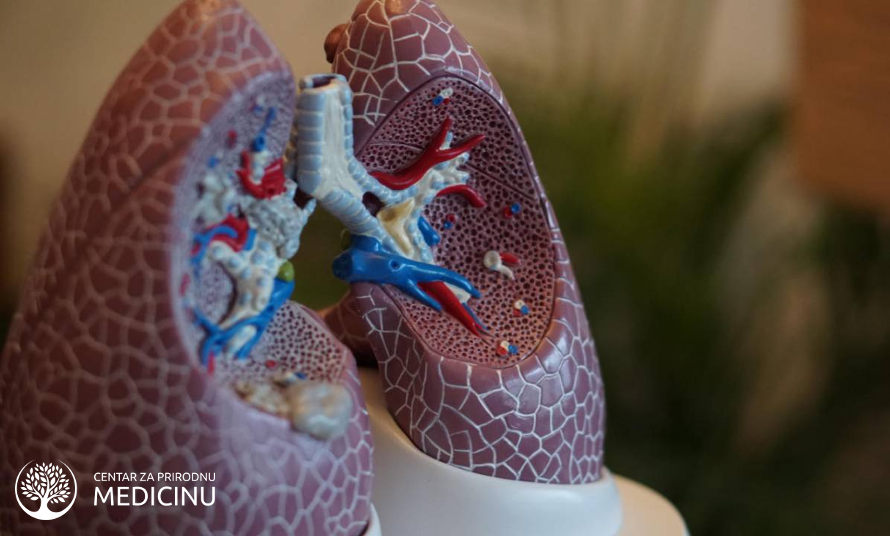

Upala pluća (Pneumonija) – uzrok, simptomi lečenje prirodnim putem

Upala pluća se često može zanemariti jer se simptomi nekada ne izraze u punini. U svakom slučaju je treba tretirati do maksimuma jer posledice mogu oslabiti pluća i učiniti ih time podložnim za ponovne upale.